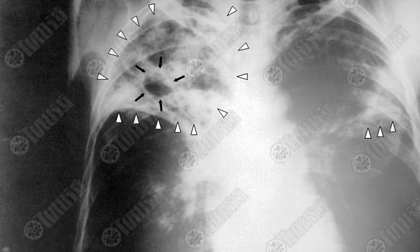

ตรวจวัณโรควิธีใหม่รู้ผลในเวลา 100 นาทีเดิมต้องคอย 3 เดือน

องค์การอนามัยโลกสนับสนุนให้ใช้วิธีตรวจสอบผู้ป่วยวัณโรควิธีใหม่ ในการวินิจฉัยโรครู้ผลได้ในเวลาเพียง 100 นาที แทนวิธีตรวจสอบดั้งเดิมที่ใช้กันมาเป็นศตวรรษแล้ว และต้องคอยรอฟังผลนานถึง 3 เดือน

วิธีการตรวจสอบด้วยการตรวจเสมหะ ทำกันมานานศตวรรษกว่าแล้ว และต้องรอฟังผลนานเกือบ 3 เดือน วิธีตรวจสอบใหม่นี้ ได้รวมเอาเทคโนโลยีดีเอ็นเอสมัย ใหม่เข้าไปด้วย สามารถทำนอกห้องปฏิบัติการที่ไหนก็ได้.